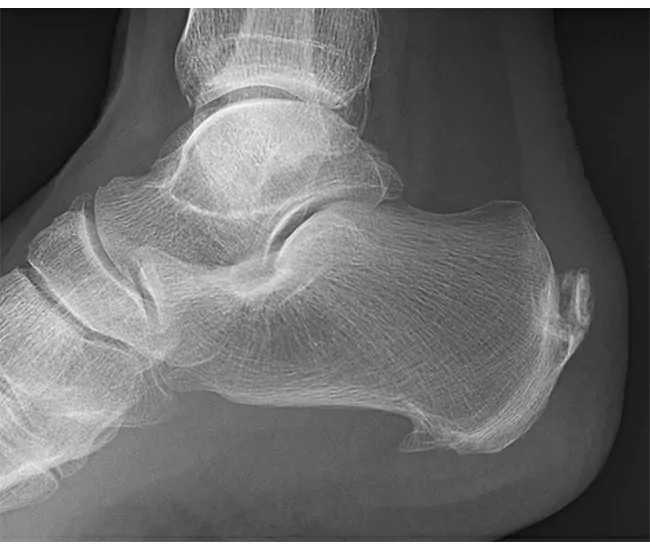

1. Calcaneal Spur – A bony growth (osteophyte) on the heel bone (calcaneus) due to prolonged stress.